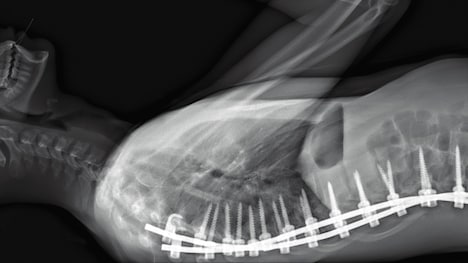

「人体の構造について」場面写真

「人体の構造について」場面写真 [高画質で見る]

身近ながら神秘のベールに包まれた“人体”をテーマとする本作。パリ北部近郊にある5つの病院のオペ室を舞台に、医師視点のカメラや内視鏡によって、脳や大腸、眼球、男性器などの外科手術や帝王切開の模様が映し出される。さらに医療従事者の心境や、死体安置所における納棺師の仕事にも迫る。